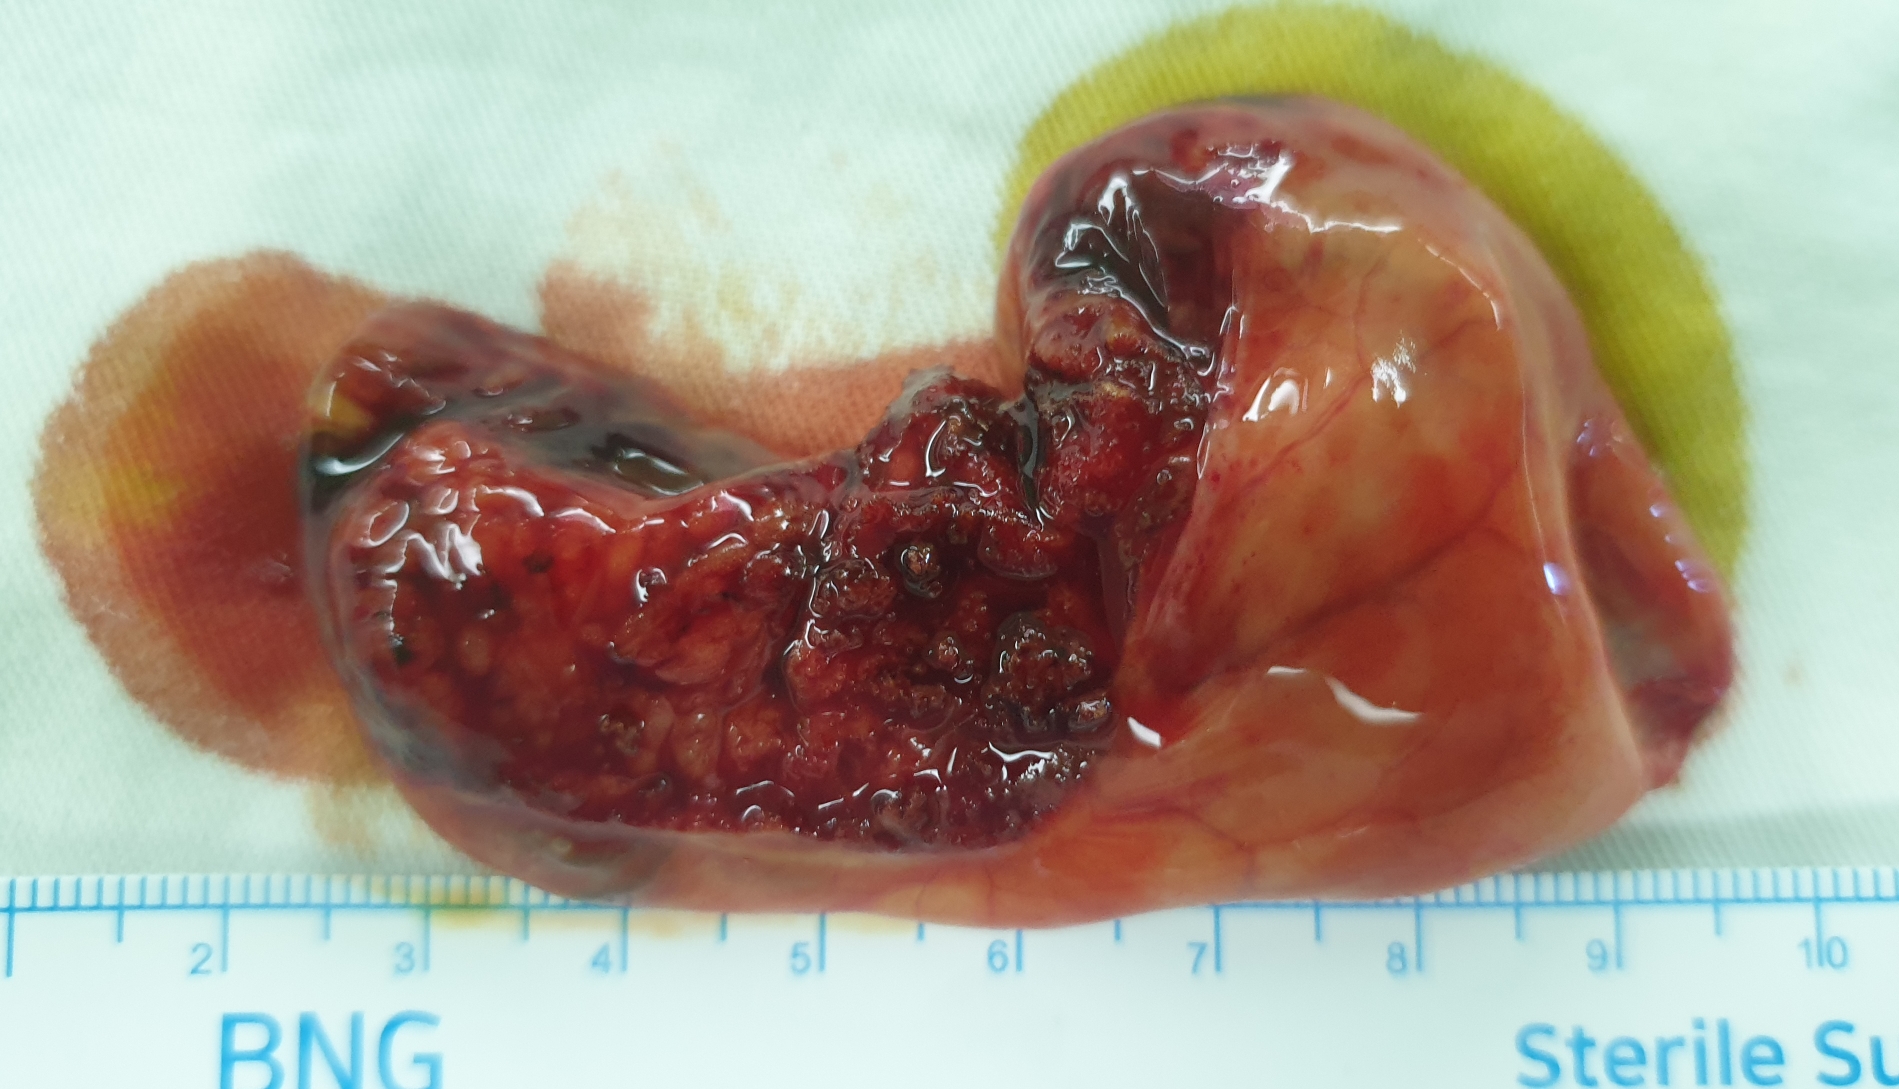

담낭 선근증으로 식후 소화불량 증상이 있던 분이었습니다.

복강경 담낭절제술을 시행했습니다.